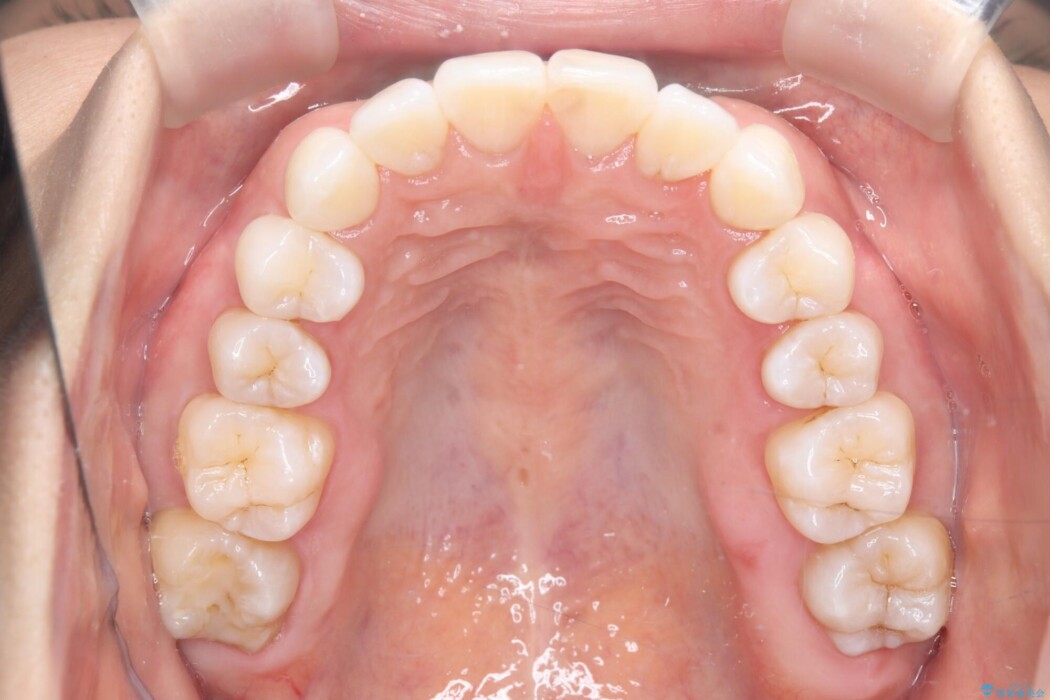

矯正検査の結果、右上7番が頬側に大きくズレており、うまくかみ合っていない状態でした。

全体的にスペース不足ではありましたが、患者様は抜歯をしたくないとのご要望だったため、上顎の裏側に「トランスパラタルアーチ(TPA)」という装置を装着し、奥歯の幅を調整しながらスペースを確保する計画を立案。

トランスパラタルアーチを用いて右上7番目の歯を内側へ誘導し、正しい位置へと修正しました。

まずはこの装置で奥歯の土台を安定させつつ、ワイヤー装置による繊細な歯の移動を組み合わせることで、非抜歯で歯列全体のアーチを整えていきました。シザーズバイトが解消されたことで、奥歯でしっかりと物を噛めるようになり、顎の動きもスムーズに改善されました。